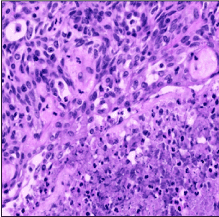

On Immunohistochemistry, the tumour cells were positive for Pan-CK, BCL-2, CK 5/6, CK14, p63 with a patchy CK7 positivity. The tumour cells were negative for CD5 and CD117. The overall features suggested a type AB thymoma (Figure 3) with an atypical type A component (Figure 4). This was also reviewed and confirmed by Dr N Kingston, Auckland Hospital.

Figure 4. Histology of Thymoma – Atypical Type A Component

Type AB thymomas are denoted as mixed thymomas containing both type A and type B areas. Both type AB and type A thymomas are generally lower grade with risk of local recurrence. The new thymoma variant, atypical type A thymoma is similar in appearance to type A thymomas in that it has spindled to oval shaped cells with few/sparse lymphocytes. However, in contrast to type A thymomas they demonstrate cytologic atypia. The WHO classification of 2015 defines it as featuring spindle to oval shaped cells with mild to moderate nuclear atypia, hypercellularity, increased pleomorphism and nuclear hyperchromasia as well as foci of necrosis or comedonecrosis. It also has an increased mitotic count of >4 per 2 mm2. All of these features are traditional features of malignancy or likely to denote a more aggressive course [1].